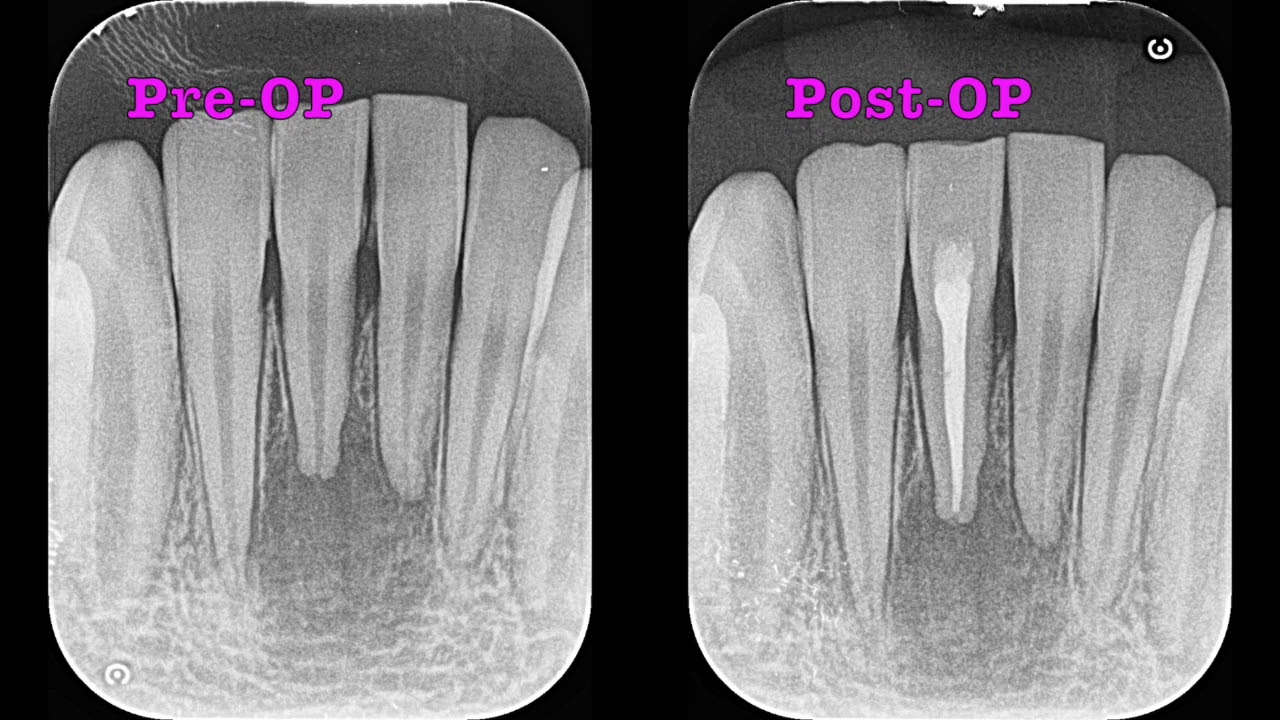

当院の「精密根管治療(初回:感染根管治療)」の予後観察についてご紹介します。

来院時、抜歯を覚悟されていた患者さまは、非常に治りが良い、当院の「精密根管治療」に大変満足されていました。

当院では、歯科用CBCT撮像から患者さまの根管形態と根尖の状態を把握し、治療が非常に困難な下顎前歯部の「根管治療」において、マイクロスコープを用いて「精密根管治療」を実施しております。